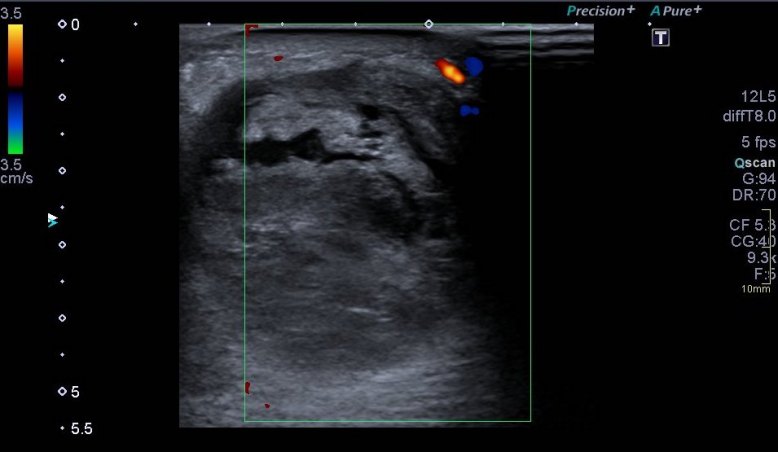

Se realiza estudio ecográfico de la «tumoración» que presenta el paciente la región postero interna de la pierna izquierda, se visualiza lesión heterogénea de 41 x 53 x 54 mm con áreas quísticas localizados sobre todo el tejido celular subcutáneo que presiona al gemelo medial, muy escasa vascularización, y áreas con sospecha de necrosis que en la ecografía se corresponden con imágenes de aspecto quístico.

Siempre es muy importante estudiar la patología en dos proyecciones, eje corto y eje largo. Medirlo y documentarlo muy muy bien. En caso de no usar pictograma, tenemos que escribir en la zona exacta donde se encuentra la lesión o la ecoestructura a estudio para que la radióloga sepa exactamente la localización.

En estos casos donde la figura patológica está muy a piel, o está muy superficial es imprescindible poner una buena capa de gel entre la piel y la sonda a fin de no presionar en exceso para no deformarla y así poder perder cierta información que puede ser relevante.